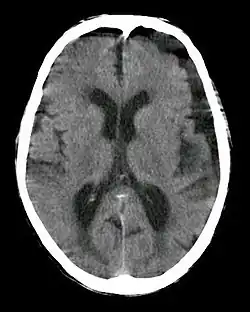

| Subdural hygroma, frontal and temporal. Man of 80 years old. | |

In CT scan, subdural hygroma will have same density as the normal CSF. Meanwhile, in MRI, subdural hygroma will have same intensity with CSF. If iodinated contrast is administered during CT scan, the hygroma will produce high density because of the contrast at 120 kVp. However, at 190 kVp, hygroma with contrast will have intermediate density.[2]

It is not uncommon for chronic subdural hematomas (SDHs) on CT reports for scans of the head to be misinterpreted as subdural hygromas, and vice versa. Magnetic resonance imaging (MRI) should be done to differentiate a chronic SDH from a subdural hygroma, when clinically warranted. Elderly patients with marked cerebral atrophy, and secondary widened subarachnoid CSF spaces, can also cause confusion on CT. To distinguish chronic subdural hygromas from simple brain atrophy and CSF space expansion, a gadolinium-enhanced MRI can be performed. Visualization of cortical veins traversing the collection favors a widened subarachnoid space as seen in brain atrophy, whereas subdural hygromas will displace the cortex and cortical veins.